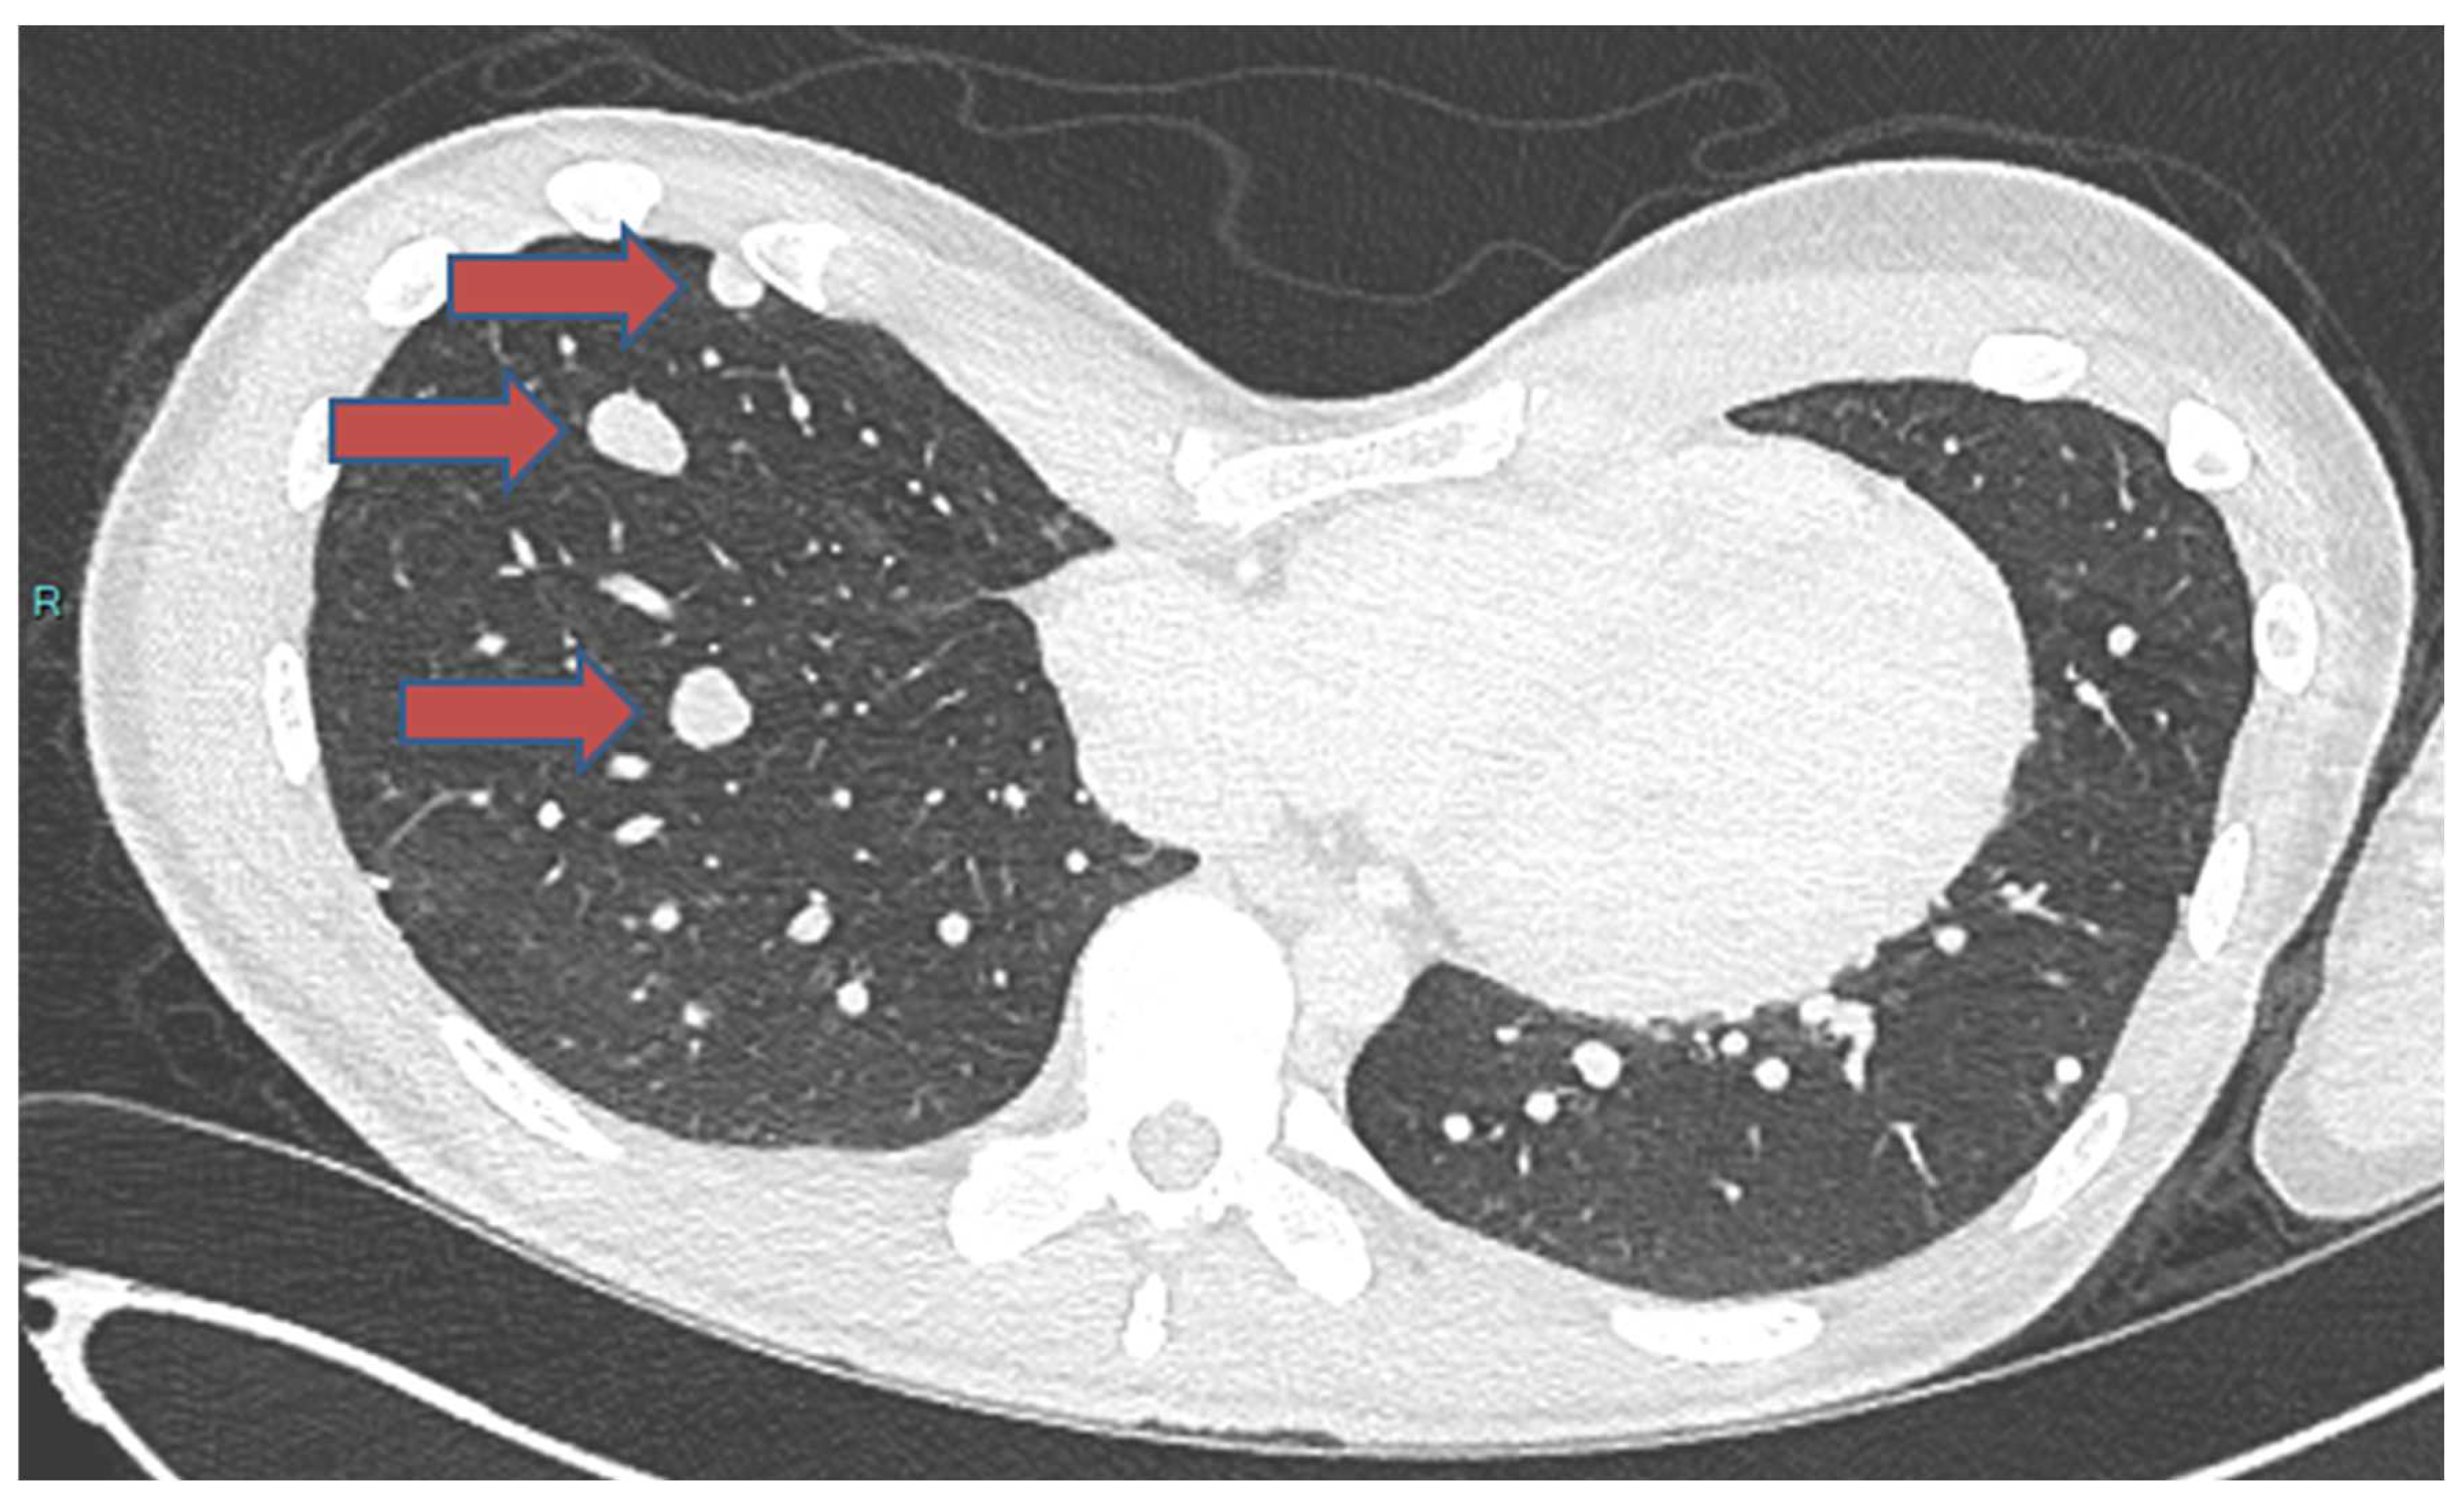

- Samargandi, R.; Bernard, M.; Miquelestorena-Standley, E.; Le Nail, L.R. Efficacy of denosumab treatment for lung metastasis secondary to proximal humerus chondroblastoma. Saudi Med. J. 2024, 45, 633. [Google Scholar] [CrossRef]

| Samargandi. [93] | 19/M | Proximal humerus | Lung, shoulder metastasis to lung | Late metastasis without local recurrence | Benign | 1 year 3 months | 2 years | Alive at last follow-up | Partial metastasectomy and denosumab |